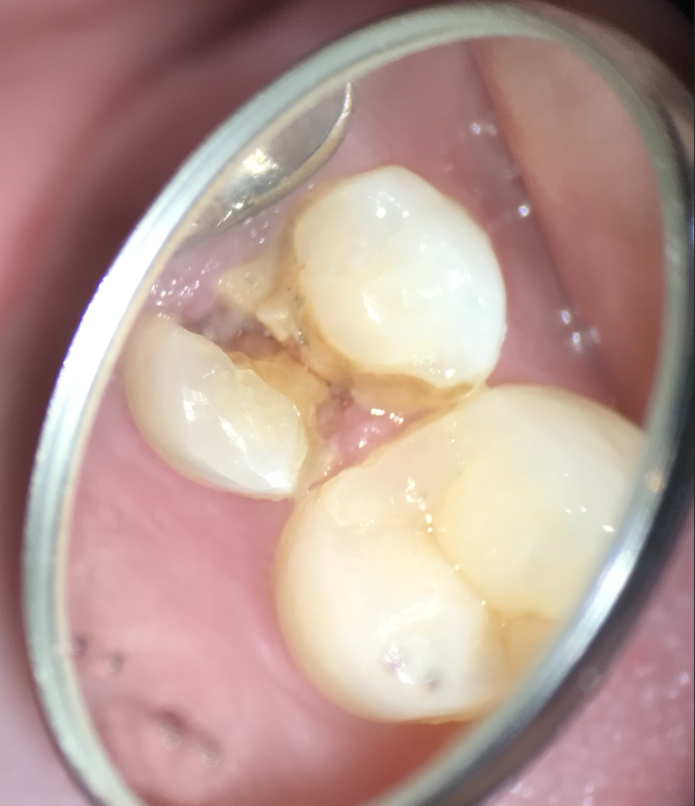

- 顕微鏡で見ると歯の破折がはっきりします。

- 2023.01.16